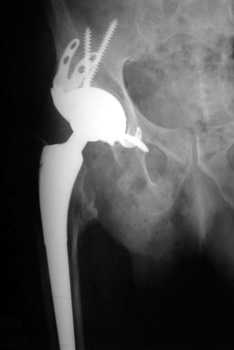

Revision Arthroplasty

• Larger components to fill larger bone defects secondary to loosening, osteolysis, and/or infection

• Higher incidence of fracture

• Ddx control osteotomy may have been surgically placed to aid in removal of former prosthesis

Control perforation lateral femoral cortex, reduced by cerclage cable

Revision arthroplasty (A). Proximal femur resected due to large amount of osteolysis (B).

Revision arthroplasty with long femoral stem and large phalanged cup. Note inguinal hernia containing bowel.